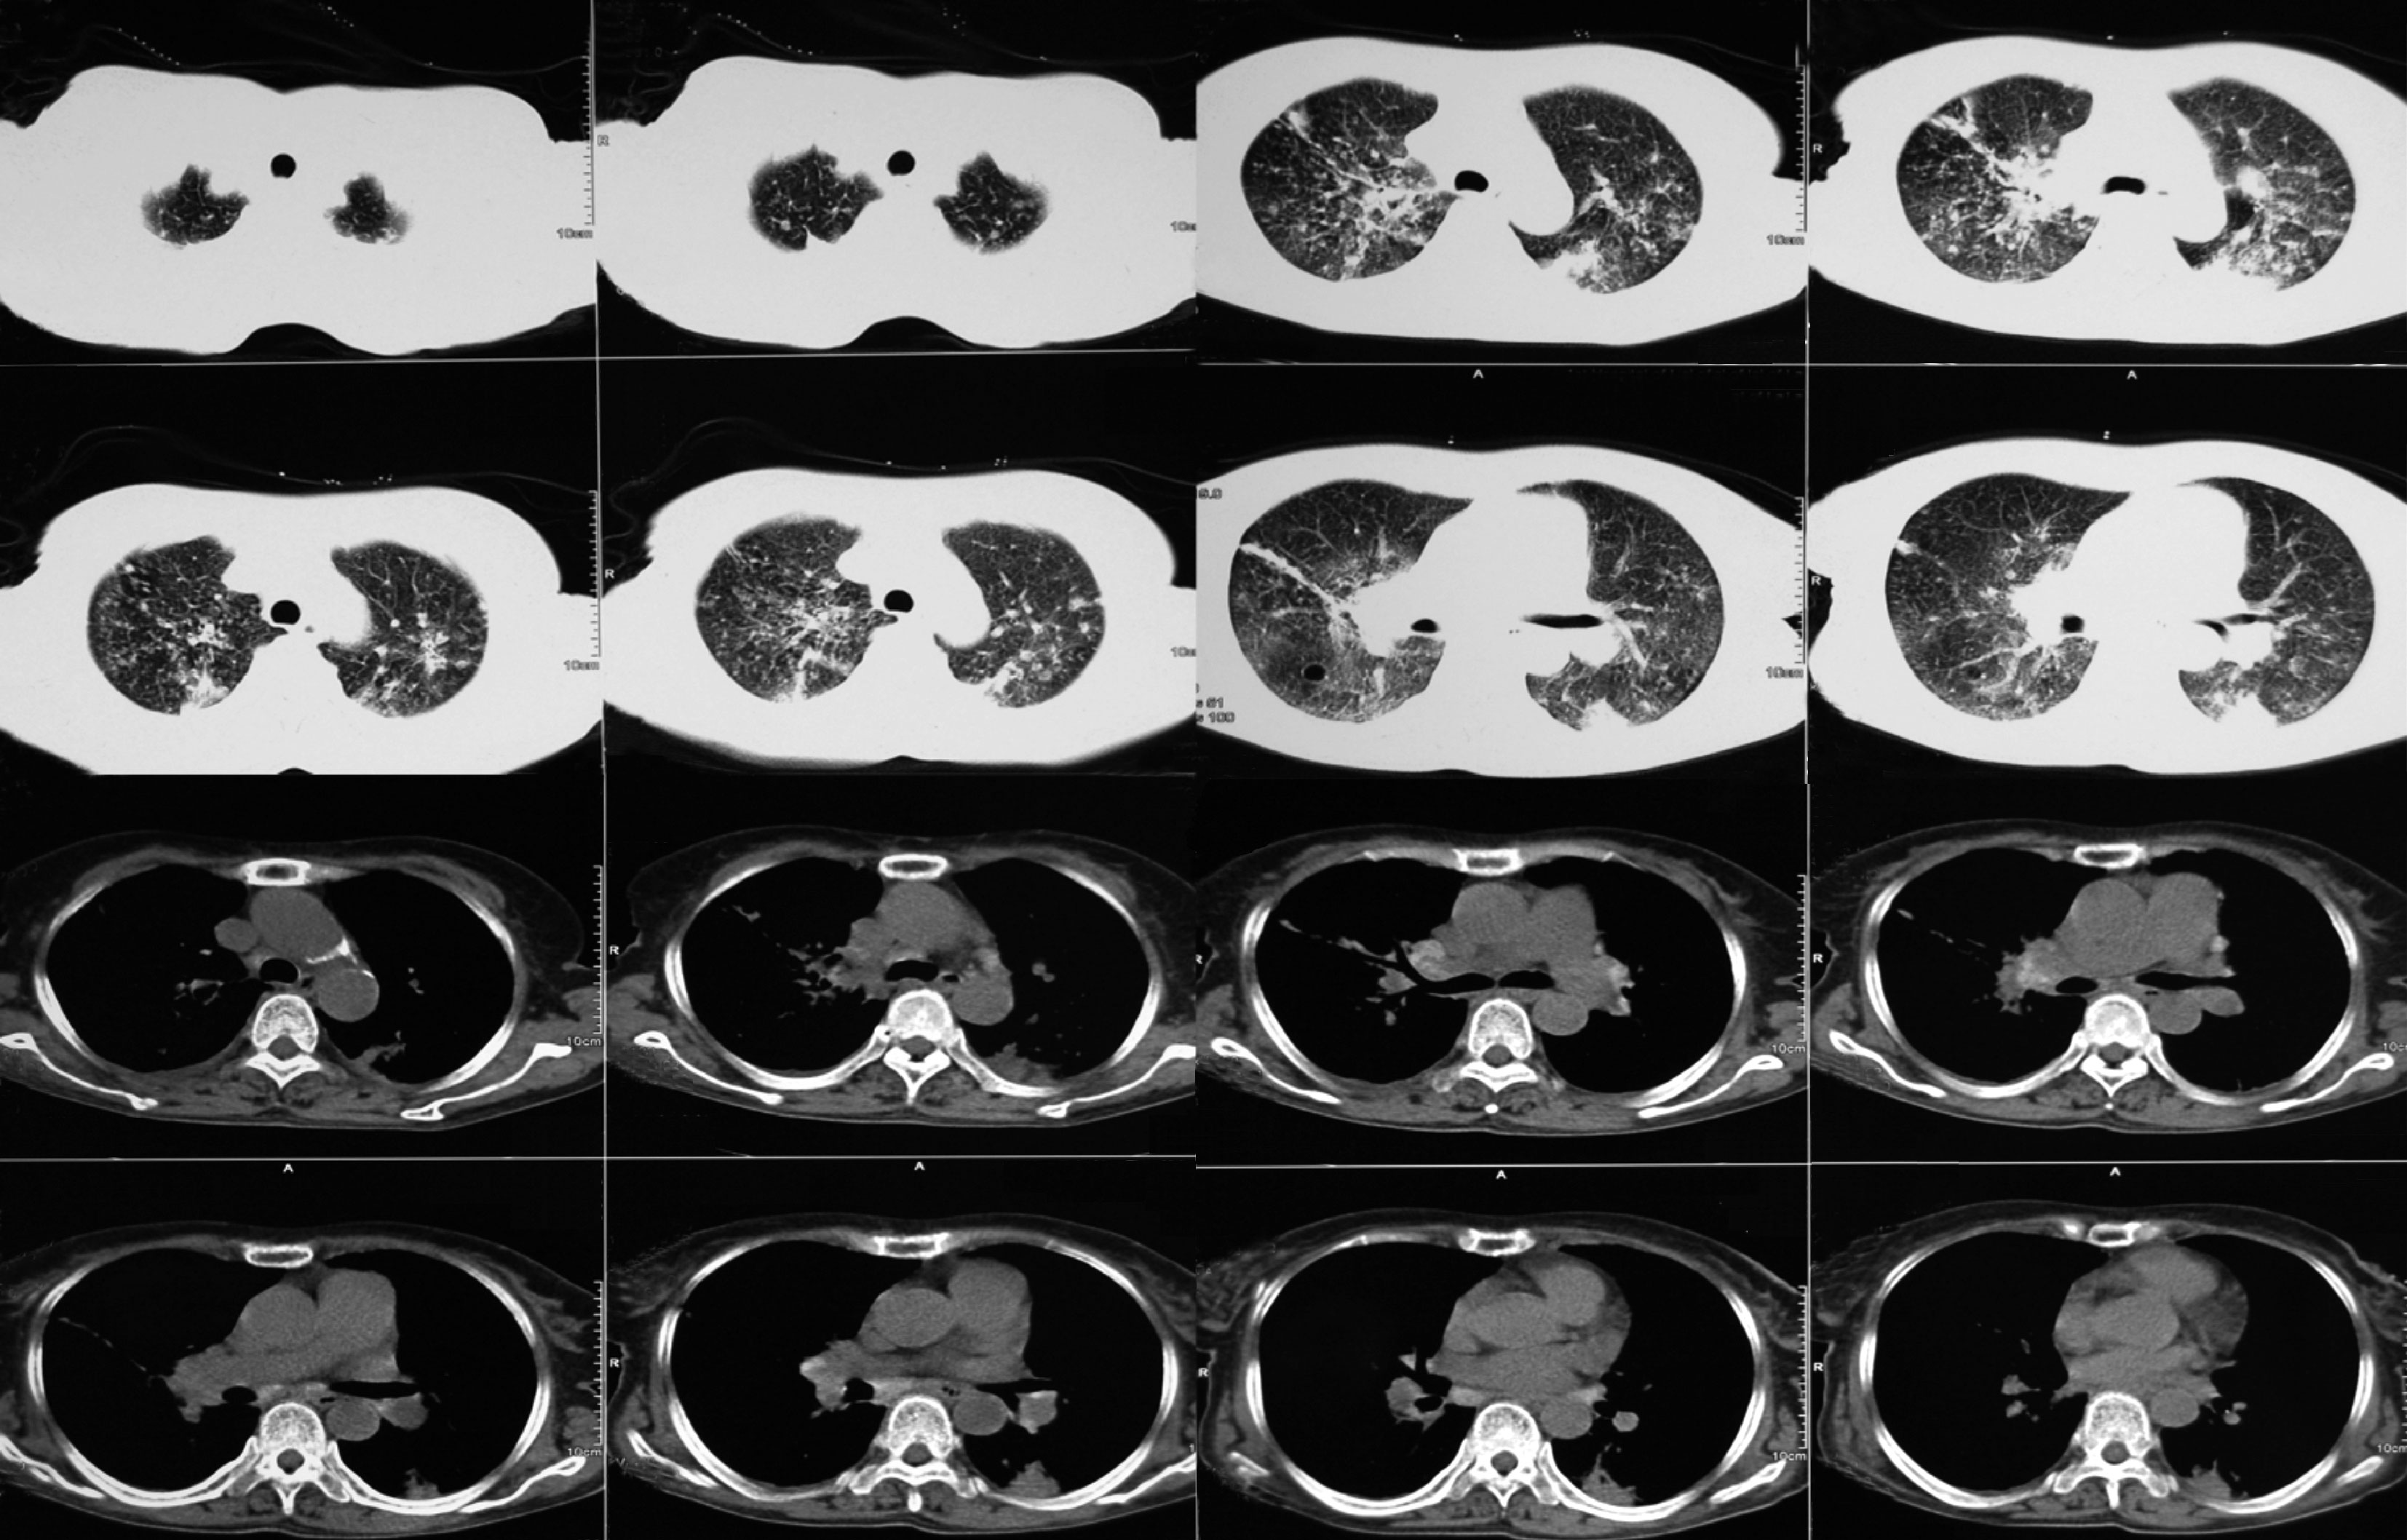

胸部CT:双肺多发斑片、结节影,以双肺上叶及下叶背段为主,多考虑肺结核;纵隔及肺门多发淋巴结肿大,部分钙化;左侧胸腔积液,双侧胸膜增厚(图10-1)。

图10-1 胸部CT

双肺多发斑片及结节影、纵隔及肺门淋巴结肿大,部分钙化

住院第28日复查心脏彩超示左心室血栓消失(图10-3),第29日CT引导下经皮肺穿刺活检病理结果回报:小灶型干酪样坏死组织,周围包裹上皮样细胞、多核巨细胞,伴间质、纤维组织增生,慢性炎性细胞浸润。抗酸染色找到抗酸杆菌(见文末彩图10-4)。

出院后继续四联抗结核治疗,同时口服华法林(据INR结果调整剂量)。抗凝治疗3个月后患者腹痛消失,当地医院复查腹部B超脾梗死消失,停用华法林。抗结核治疗1年后咳嗽、气短症状消失,复查胸部CT肺部斑片影消失,停用抗结核药。随访至今患者未诉特殊不适。